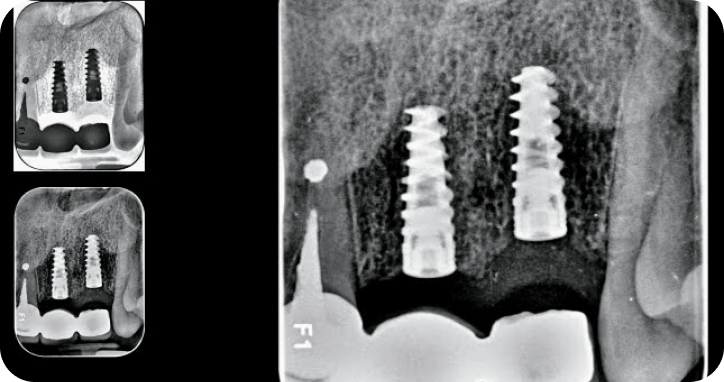

Implantes

Son tornillos en titanio que reemplazan las raices de los dientes.

Implantes de uso en la clínica

MISS, ADIN , ALPHABIO.

Perimplantitis (Infección del hueso alrededor del implante) suscausas pueden ser mala higiene, bruxismo, pacientes diabeticos no controlados, periodontitis adyacentes. Rechado del organismo 5%.

Casos